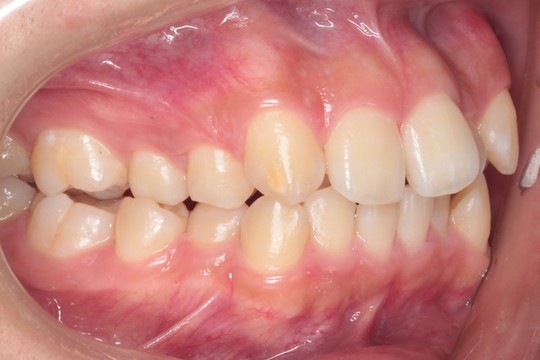

治療前

『交叉咬合(こうさこうごう)』は

上下の歯の関係が一部反対になっている状態の歯並びです

クロスバイトとも呼ばれます 今回は右の5番目あたり(向かって左側)に起きています

『叢生(そうせい)』は

草むらを表す『叢(そう)』のように込み入った歯並びを指します

日本人に多い、前歯がデコボコした歯並びです

このレベルの叢生であれば、誰しも抜歯矯正を考えると思います

しかし今回は、抜歯矯正を行うと後のかみ合わせなどのリスクが高く感じたため

親知らずの抜歯にとどめ、奥歯をそのスペースに送ることで

前歯が収まるスペースを得ることを考えました